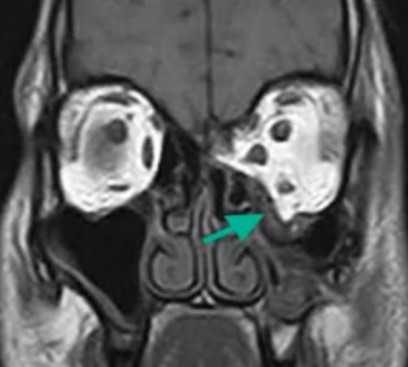

Взрывной перелом орбиты на МРТ (изменения указаны стрелкой)